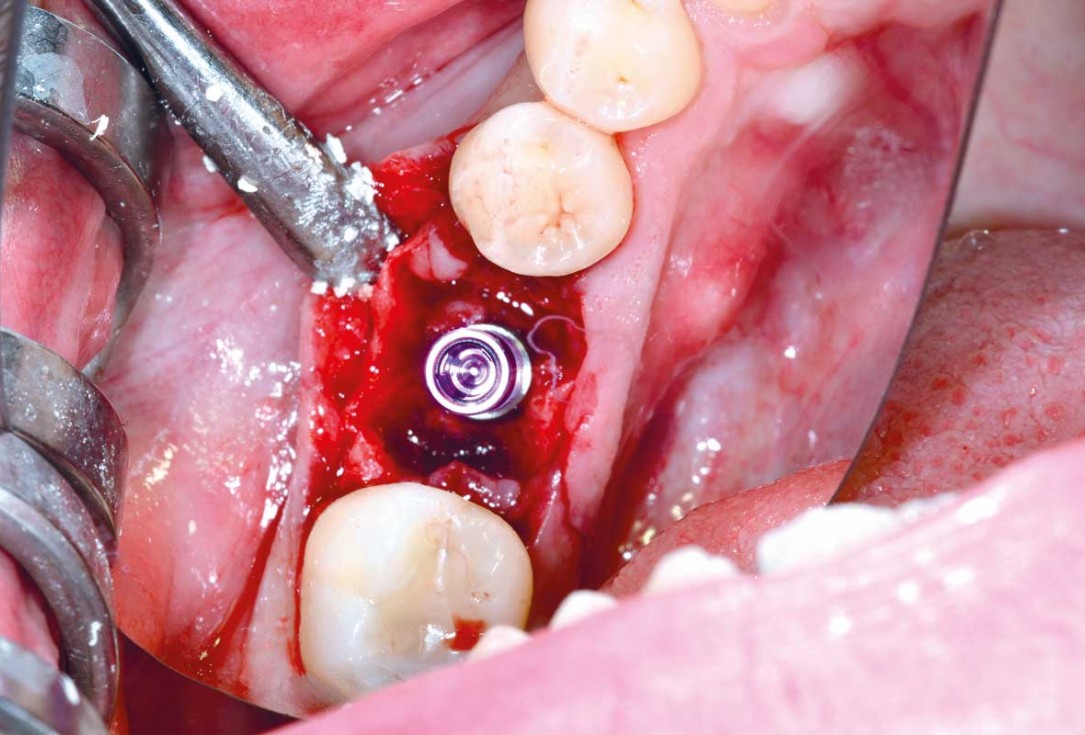

17/25 - Re-entry three months post-operativeImmediate implant placement and peri-implant bone augmentation with cerabone® plus - Dr. R. Block Veras